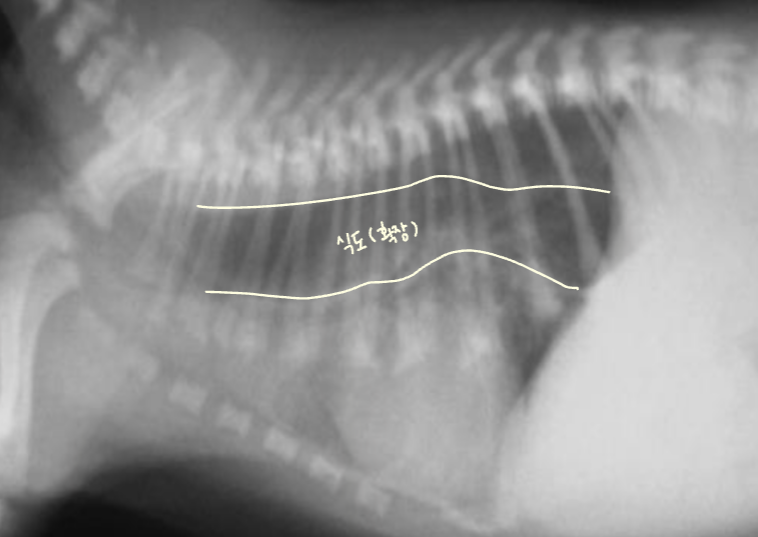

1. Esophagus (์๋)

- ์๋ : ์ฐ๋ถ์กฐ์ง, ํก๊ฒฉ๋ง์ ๊ฑฐ์ณ ํ๋ง์ ๋ซ๊ณ ์๋ก ๋ค์ด๊ฐ.

- ์ ์์ ์ผ๋ก๋ ๊ณต๊ธฐ๊ฐ ์์ด collapsed. gas๊ฐ ์ฐจ๋ฉด ๋ณด์ผ ์ ์์.

- ์ ์ ์๊ฒฌ

- ๋ง์ทจ๋ ํฅ๋ถ์ ์ํด ์ ์์ ์ผ๋ก ์๋๋ด ๊ฐ์ค๊ฐ ๋ถ๋ถ์ ์ผ๋ก ์ถ์ ๋ ์ ์์.

- ํ๊ฐ ์ ๊ตฌ๋ถ ์๋์ ๋ฏธ์ฝํ ํ์ฅ๊ณผ ์๋ ์ฃผํ์ ๋ณํ์ ์ ์.